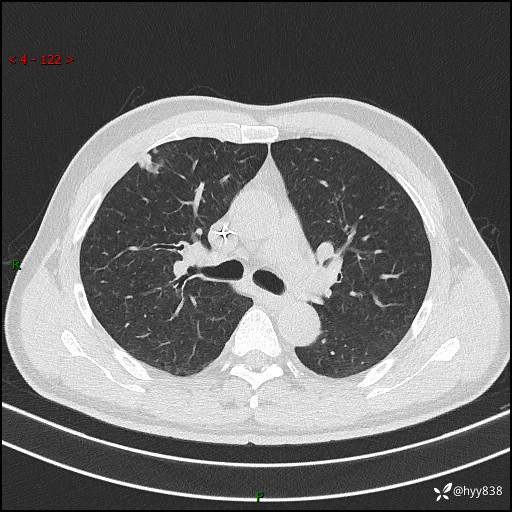

现病史:者10余天前因胸闷就诊于我院心血管内科,行胸部CT提示右肺上叶结节(24mm×16mm),考虑肿瘤性病变可能。无畏寒、发热、盗汗,无咳嗽咳痰,无咯血,无胸痛,无呼吸困难等不适,未予特殊处理。今为求进一步诊治,前来我院就诊,门诊以“肺结节待查”收住入院。 患者自起病来精神、食欲、睡眠尚可,体力下降,体重无明显变化。

胸部CT平扫+增强